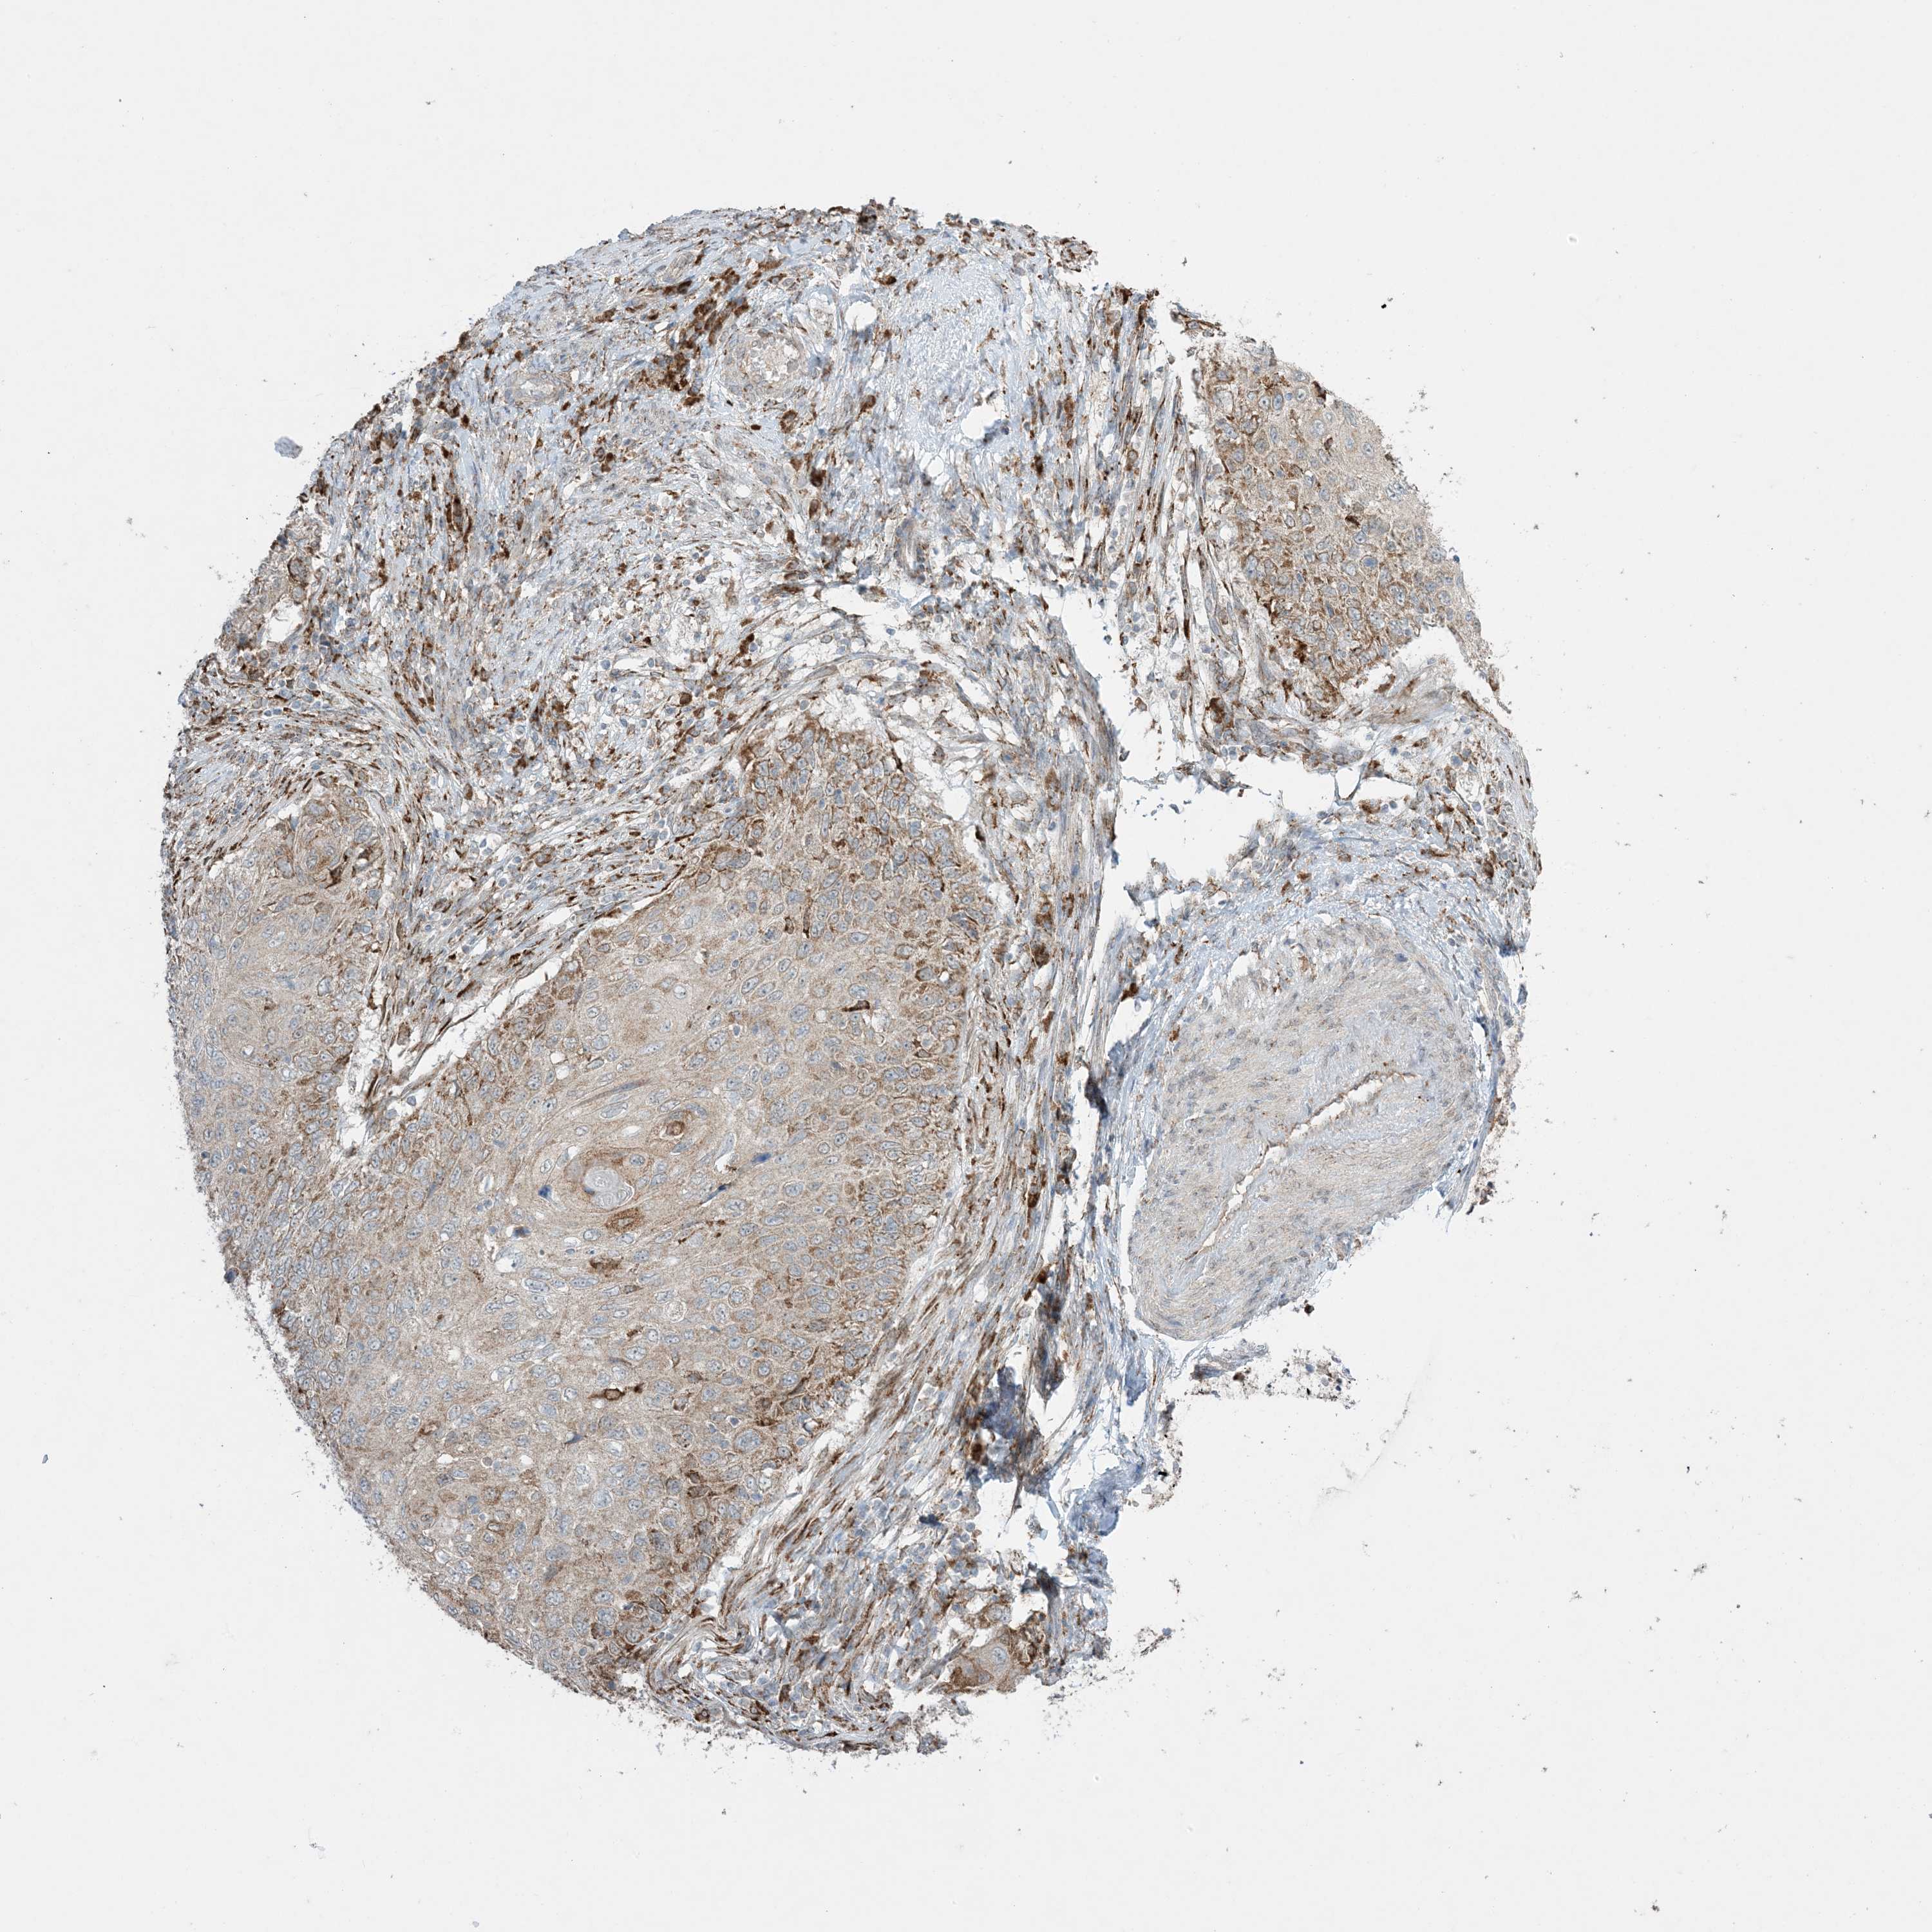

CERVICAL CANCER - Protein expressioni

A mouse-over function shows sample information and annotation data. Click on an image to view it in a full screen mode. Samples can be filtered based on level of antibody staining by selecting one or several of the following categories: high, medium, low and not detected. The assay and annotation is described here.

Note that samples used for immunohistochemistry by the Human Protein Atlas do not correspond to samples in the TCGA dataset.

Antibody stainingi

Antibody staining in the annotated cell types in the current human tissue is reported as not detected, low, medium, or high, based on conventional immunohistochemistry profiling in selected tissues. This score is based on the combination of the staining intensity and fraction of stained cells.

Each image is clickable and will lead to virtual microscopy that enables deeper exploration of all samples and also displays staining intensity scores, fraction scores and subcellular localization as well as patient and tissue information for each sample.

Antibody HPA001536

Antibody CAB035996

Staining

High

Medium

Low

Not detected

Intensity

Strong

Moderate

Weak

Negative

Quantity

>75%

75%-25%

<25%

None

Location

Nuclear

Cytoplasmic/membranous

Cytoplasmic/membranous,nuclear

Squamous cell carcinoma, NOS

Adenocarcinoma, NOS